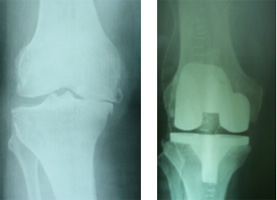

TOTAL KNEE REPLACEMENT